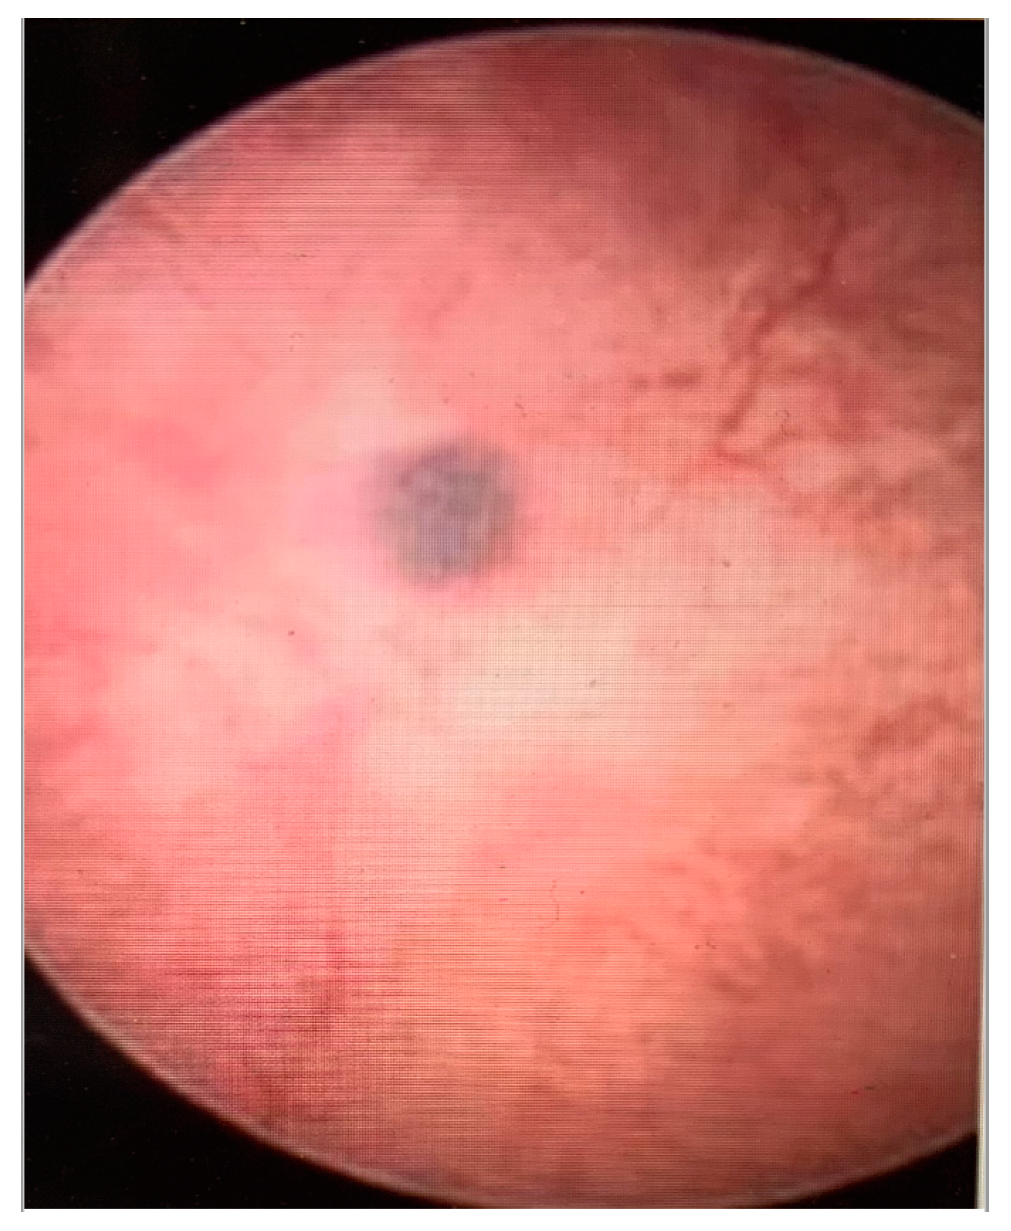

- Haemorrhagic cystic lesions presenting with a dark blue or chocolate brown appearance (Figure 5)